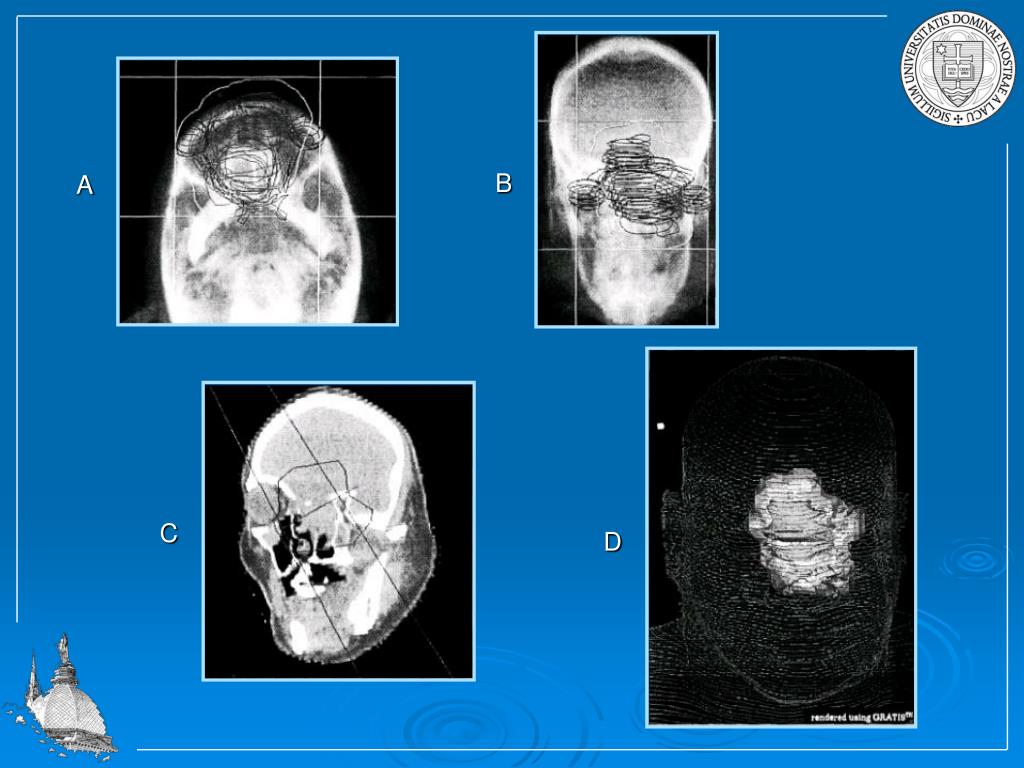

14. B A C D

13. Treatment plan needs to be carefully designed, should rely on careful localization of tumor with modern imaging techniques (CT, MRI). Dose and dose losses should be simulated (three dimensional simulation).

15. Typically, the prescribed dose depends on the size of the tumor and the specific organ which has been effected. The prescribed total doses range between 40 Gy to 70 Gy. For external beam therapy the dose will be administered over a period of five to six weeks with a daily dose ranging between 1.9 and 2.2 Gy/day (five days a week). The treatment time depends on the intensity of the radiation source!